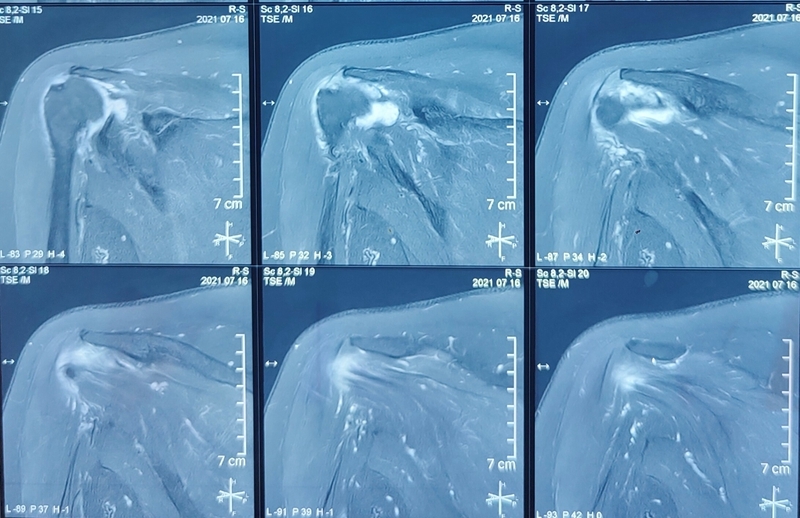

65岁女性,无明显诱因出现右肩疼痛、活动受限1年,外伤后加重2个月入院。术前右肩典型“假性瘫痪”,功能状态如图所示:

术前影像学检查示肱骨头向上移位,关节盂、肩峰和肱骨头退行性改变,典型肩袖撕裂性骨关节病(CTA)改变。